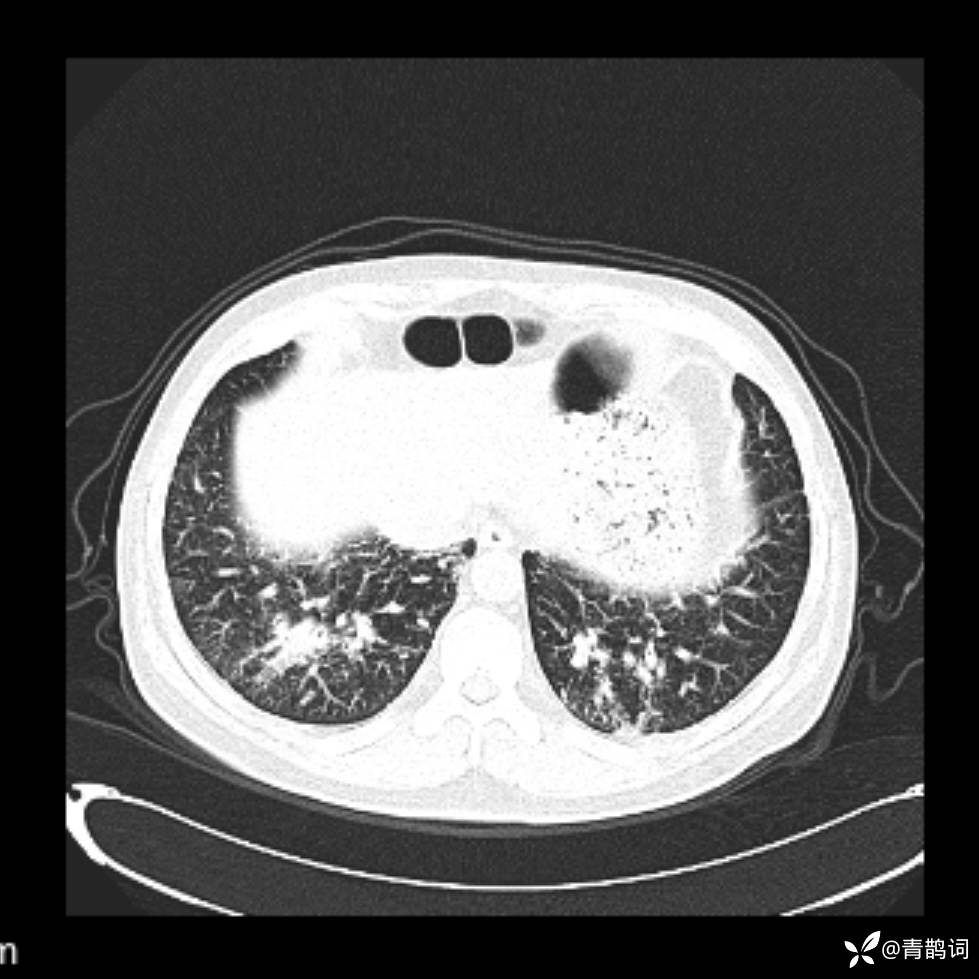

患者年龄:30岁。

患者性别:男。

简要病史:左颜面部肿胀2年,反复咳嗽咳痰,逐渐加重。

辅助检查

结合病史及影像学表现,期待评论区各位老师各抒己见~